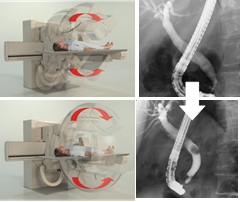

床面翻倒

床面翻倒功能可以幫助醫(yī)生分辨結(jié)石影和氣泡影、膽管內(nèi)造影劑引流或PTC穿刺引流時也需要床面的翻倒功能才能實現(xiàn)。